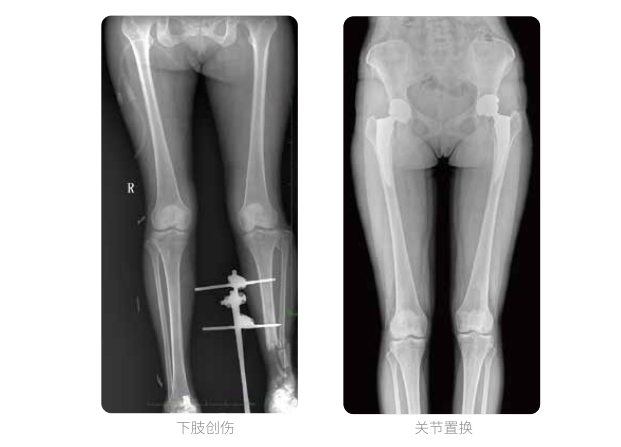

雙下肢臨床影像

髓內(nèi)釘手術(shù)是骨科、手足外科中常見的微創(chuàng)型手術(shù)方式,患者隨訪時(shí)需拍攝置入在股骨、肱骨處的較長(zhǎng)髓內(nèi)釘。PLX8600視野拍攝,能夠出色解決醫(yī)生需多次攝影再拼接的痛點(diǎn)。一次成像雙下肢,即拍即得,高效率,無需拼接。工作站軟件自帶的測(cè)量功能方便醫(yī)生讀取雙下肢長(zhǎng)度數(shù)據(jù),助力準(zhǔn)確診斷。

動(dòng)態(tài)DR所具備的全脊柱、全下肢全景成像技術(shù)檢查,能夠更加清晰的顯示患者病情變化情況,對(duì)骨科疾病患者的全脊柱、全下肢病變情況圖像展示更加具有完整性,對(duì)患者在自然狀態(tài)下的應(yīng)力情況展示較為全面,有助于骨科疾病患者臨床診斷效果的提升,對(duì)患者臨床治療方案的科學(xué)制定有著積極的作用。